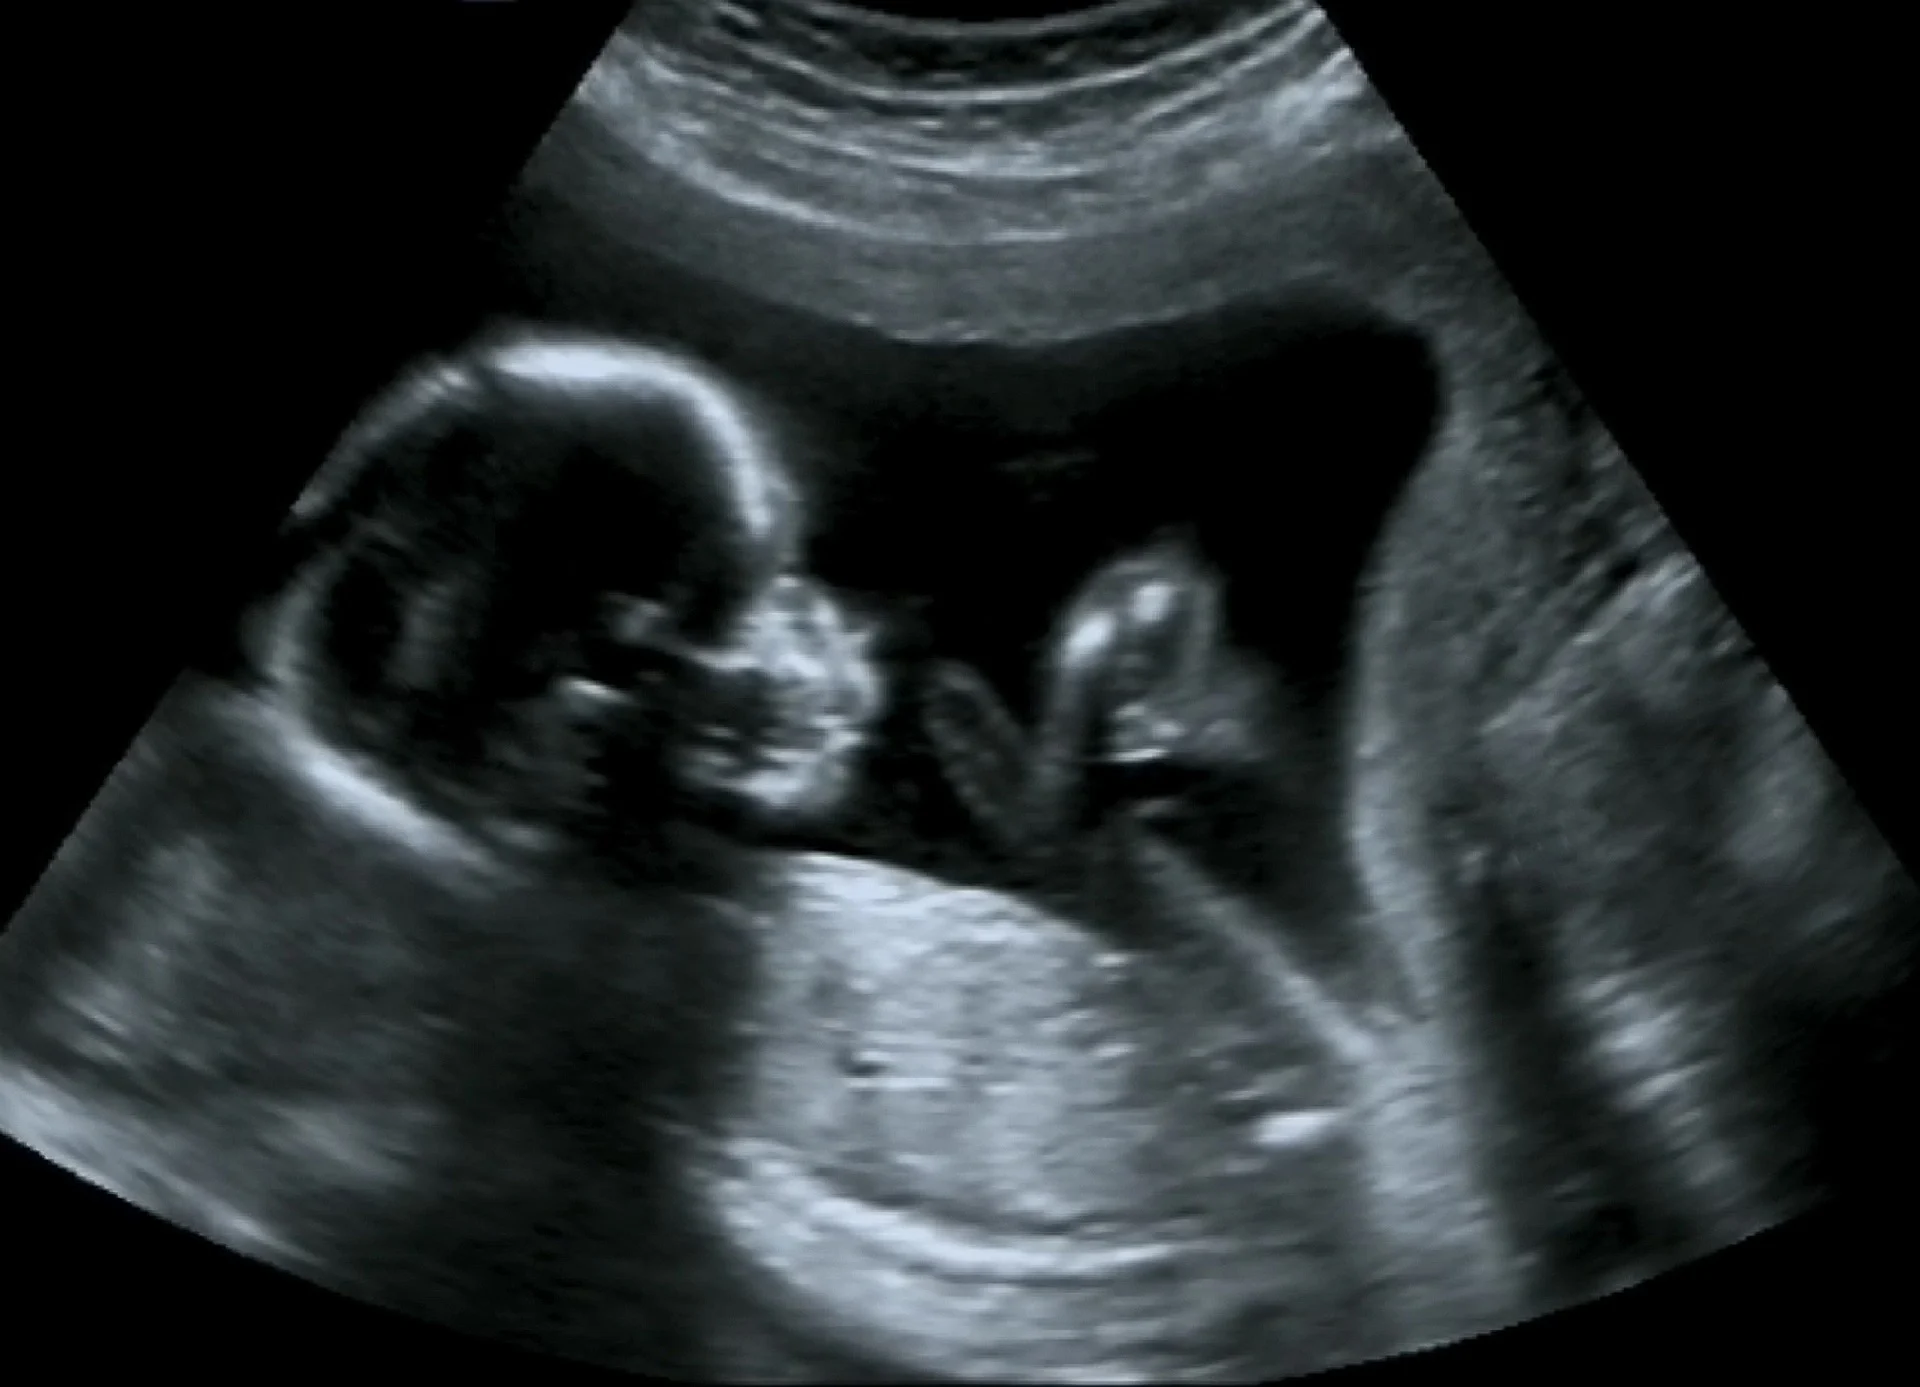

הריון קריפטי ניתן לאבחן בדרכים בהן מאבחנים הריון רגיל, כמו למשל בדיקת אולטראסאונד, בדיקת דם, או בדיקת הריון.

2. אולטרסאונד